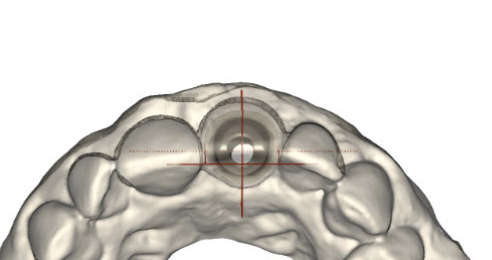

(20.)  Molar custom abutment.

Figure 20

(21.)  Molar custom abutment.

Figure 21

(22.)  Molar custom abutment.

Figure 22

(23.)  Molar custom abutment.

Figure 23

(24.)  Molar custom abutment.

Figure 24

Following the recommendations of Yi, the transmucosal portion of the prosthetic connections should be flat or concave in profile diverging no more that 30 degrees from the long axis of the implants.19 Standard abutment profiles which are flat or convex in profiles are good examples to follow (Figure 19). Following Yi's recommendations individual posterior custom abutments with narrow implants should have flat or concave transmucosal profiles like a standard implant abutment with convex intaglio shapes like pontics that are cleanable with dental floss19 (Figure 20 through Figure 28).